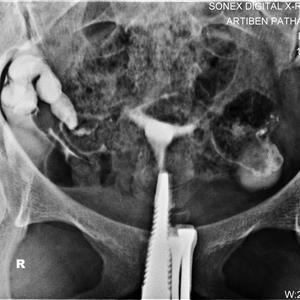

HSG ::; HYSTEROSALPINGOGRAPHY

IT IS DYE STUDY OF UTERUS AND BOTH FALLOPIAN TUBES FOR PATENCY OR BLOCK

IT IS DONE ON IITV X.RAY TABLE ,DYE INJECTION BY GYENECOLOGIST.